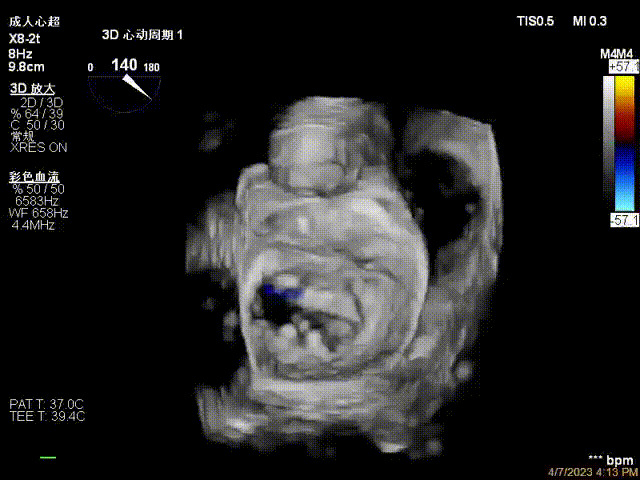

術(shù)后超聲顯示二尖瓣反流消失,瓣膜夾穩(wěn)定

接受治療的是一例器質(zhì)性重度二尖瓣反流(DMR)患者,主訴“反復(fù)活動后胸悶,氣促3年余”。術(shù)前超聲顯示,雙房增大,二尖瓣脫垂伴重度反流,輕度三尖瓣反流,輕度肺高壓,升主動脈增寬。手術(shù)經(jīng)股靜脈-房間隔入路,采用全身麻醉插管,在TEE和DSA引導(dǎo)下完成房間隔穿刺。置入JensClip瓣膜夾系統(tǒng)后,在左房調(diào)整瓣膜夾的位置和軸向,后進(jìn)入左室,在TEE引導(dǎo)下捕捉二尖瓣前后瓣葉,并關(guān)閉瓣膜夾。經(jīng)TEE反復(fù)確認(rèn)手術(shù)效果后最終鎖定并釋放瓣膜夾。術(shù)后即刻超聲顯示瓣膜夾位置穩(wěn)定,功能良好,術(shù)前二尖瓣反流4+,術(shù)后0反流,肺靜脈逆流和左房壓都顯著好轉(zhuǎn),手術(shù)圓滿成功(以上數(shù)據(jù)都來源于醫(yī)院的臨床記錄)。術(shù)后患者狀態(tài)良好,目前已安排出院。